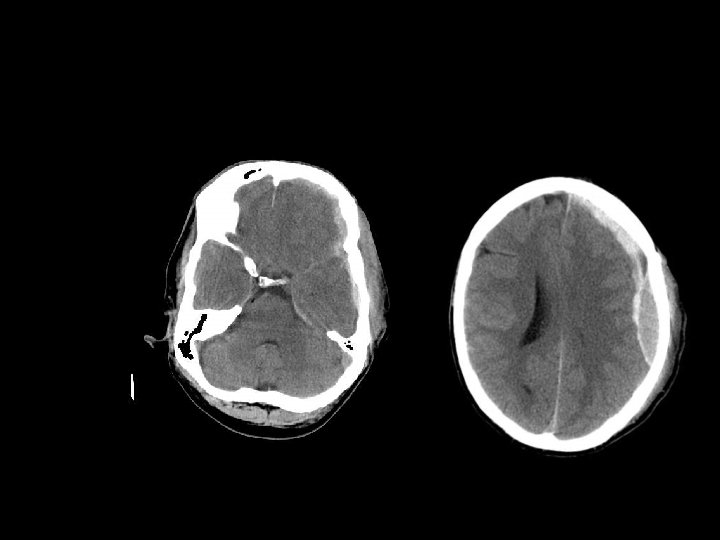

EPIDURAL HEMATOMA n Berlokasi antara skull dan periosteum n Akibat laserasi arteri meningea media atau vena dural n Dibatasi oleh sutura n Bentuk lentiform / bikonveks

PENANGANAN EDH n EDH > 30 cm 3 harus dievakuasi n EDH < 30 cm 3 dan ketebalan <15 mm dan pergeseran midline < 5 mm dan GCS >8 dapat diobservasi dengan serial CT